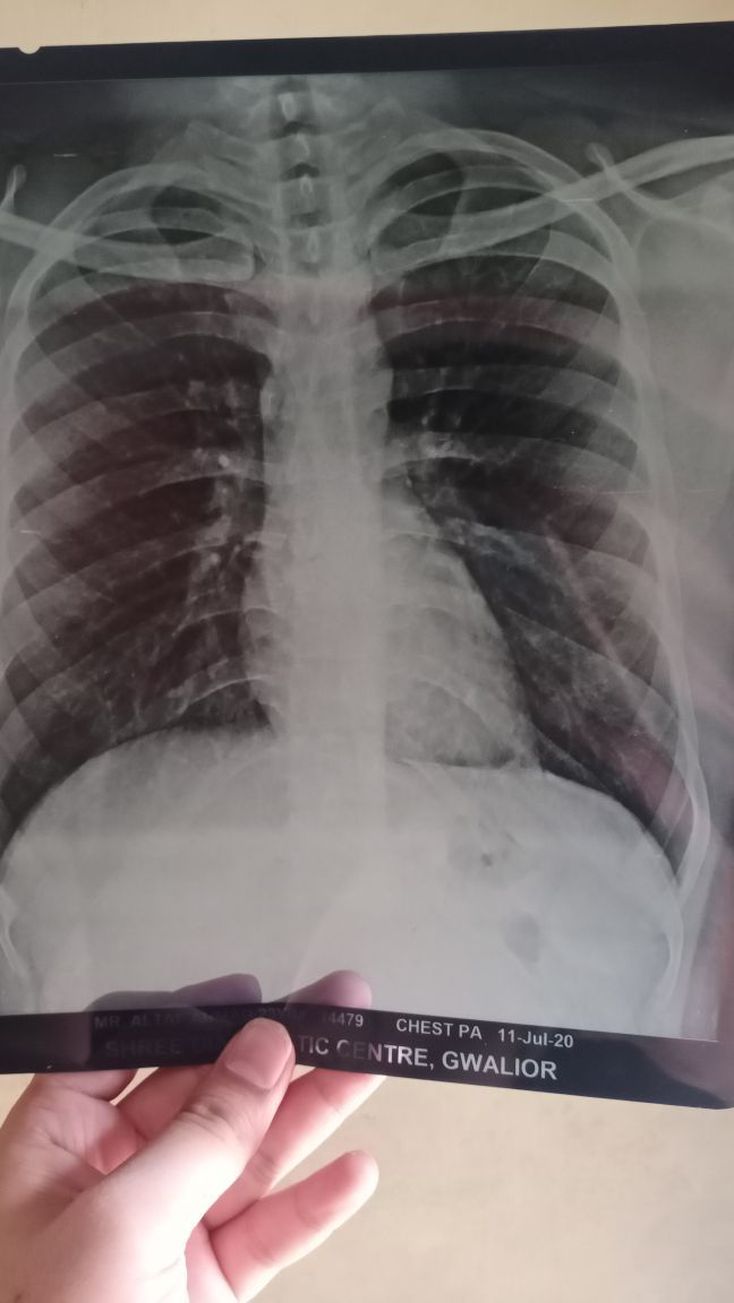

There is slight rotation. Image could be better exposed as it is difficult to see the spine behind the cardiac silhouette. There is no obvious rib fracture. Adequate inspiration, noted there is flattening of the diaphragm suggesting of possible emphysema/ chronic lung disease. Under the PA exposure, there is no cardiomegaly as the ctr is less than 0.5.